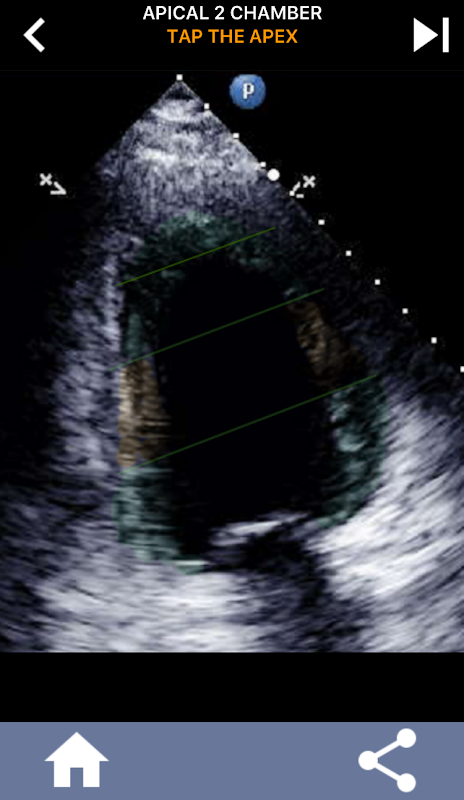

Questa app contiene tutte le viste eco che mostrano il miocardio segmentato AHA e ti chiede di toccare il segmento corretto. Personalmente trovo che il quiz ripetitivo funzioni al meglio per me quando ho bisogno di imparare / memorizzare rapidamente l'argomento. Se sei uno studente di ecografia che studia eco / TTE, penso che questo sarebbe un eccellente complemento ai tuoi studi.